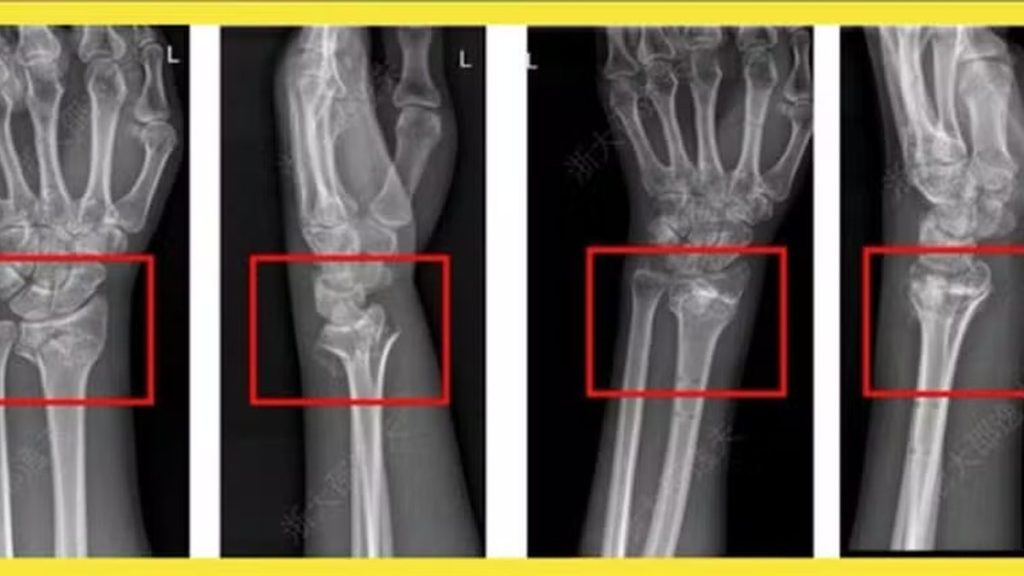

O tratamento inovador é aplicado em forma de uma única injeção, capaz de “colar fragmentos ósseos quebrados em apenas três minutos”, de acordo com a reportagem. Em um caso experimental, um paciente com fratura no punho recebeu a injeção por uma incisão de apenas 3 cm e teve a fratura consolidada no mesmo período, sem complicações, informou o “Cho Sun Daily”.